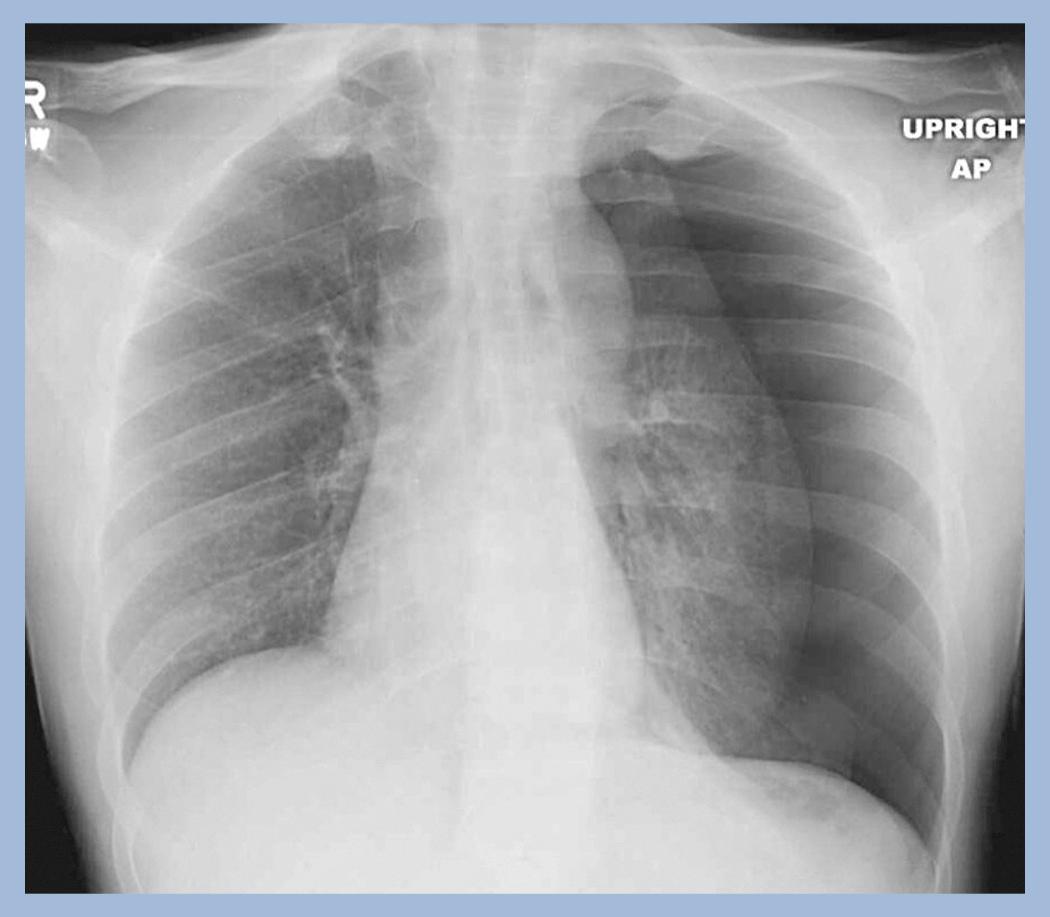

• Common uses for conventional radiography include the ubiquitous chest x-ray, plain films of the abdomen, and virtually every initial image of the skeletal system to evaluate for fractures or arthritis. Fig. 1.2 contains our first Case Quiz, this one related to conventional radiography ( Fig. 1.2 ).

Fig. 1.2, CASE QUIZ 1.